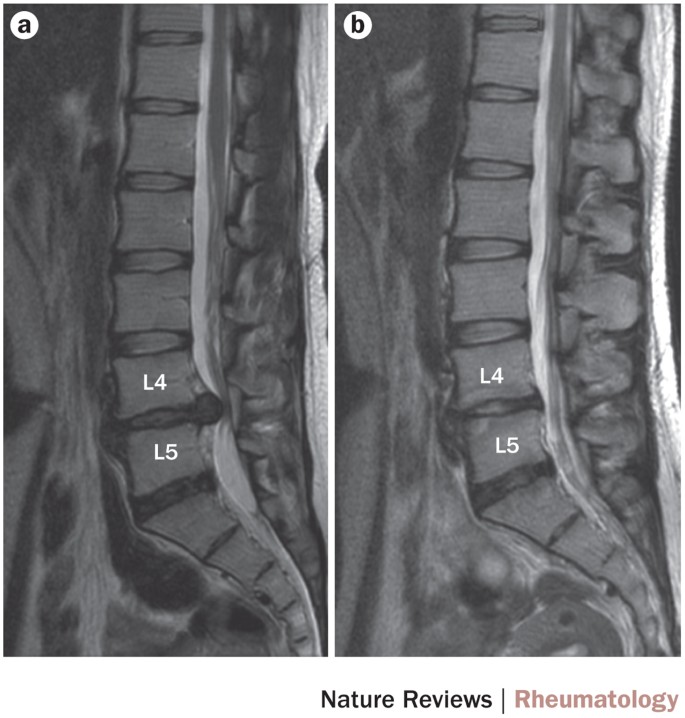

Stem Cell Therapy For Intervertebral Disc Regeneration: Obstacles And  Solutions | Nature Reviews Rheumatology Source: nature.com